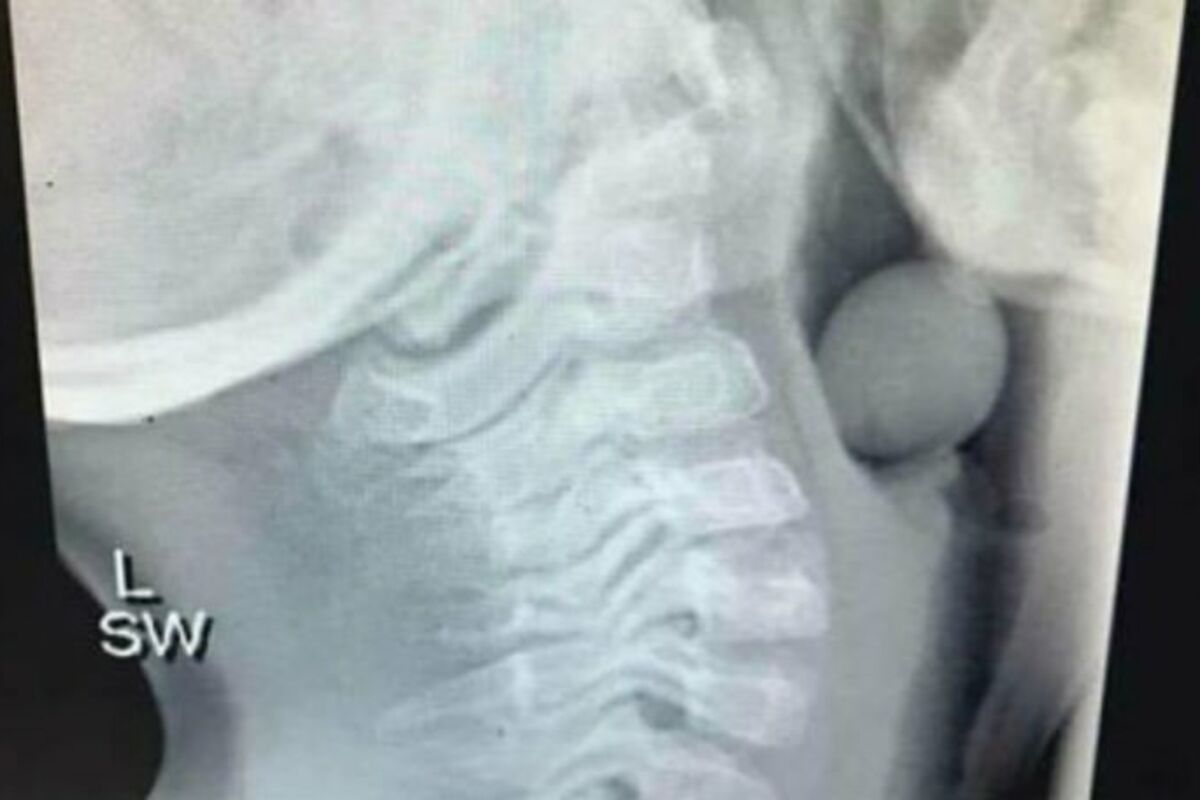

Kada je dečak stigao u dečiju bolnicu u Atlanti u Džordžiji, doktori su uradili rendgen koji im je omogućio da vide bežičnu slušalicu odmah ispod njegovog grudnog koša. Rekli su porodici da puste da slušalica prirodnim putem izađe iz dečakovog tela.